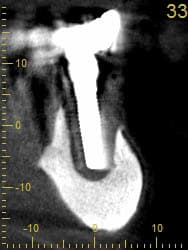

petit cas où j'ai expliqué à la patiente que là , maintenant il fallait intervenir .

bientôt la suite ...

et bien la suite c'est ça .

et évidement, ça arrive quand c'est pas le moment.

Tu veux dire que désormais, avec la perte de deux implants contigus avulsés pour cause de péri-implantite, le all on four est transformé en all on two?

82 ans

pose des implants par un praticien de Metz il y a10 ans. aucun problème particulier.

la prothèse venait d'être faite juste un peu avant le rachat du cabinet.

pratiquement aucune visites en 10 ans ...

la patiente est venue me consulter car elle souhaité la même chose au maxillaire. c'est là que j'ai découvert le pot aux roses il y a 3-4 semaines.

je lui ai dit que pour moi il était urgent de virer les implants et de prévoir une reconstitution osseuse au plus vite.

réponse de la patiente pas du tout motivé ( je peux le comprendre) ; après les grandes vacances, la communion du petit dernier, le voyage au Portugal, etc.... bref pas avant 5 mois...

elle a été prévenue du risque de casse.

au final, les vis ont cassées dans les piliers multi-unit vendredi dernier.